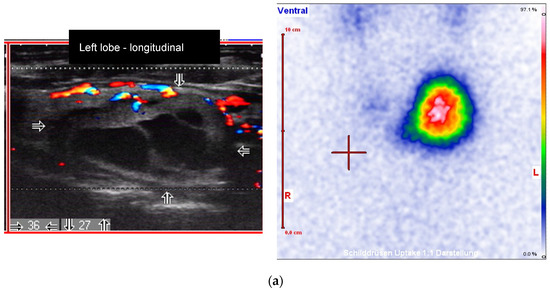

Figure 3.

Male patient with an autonomously functioning thyroid nodule (AFTN) (scintigraphy with 99mTc-pertechnetate) in the left thyroid lobe (25 × 27 × 36 mm; nodule volume 12.2 mL, arrows). (a) Before radioiodine therapy (RIT) (2016, TSH value 0.06 mU/L, no thyroid medications) with 1033 MBq (206 Gy due to reduced half-time at therapy). TIRADS classification: Kwak-TIRADS 4A (taller-than-wide shape); EU-TIRADS 5 (taller-than-wide shape); (b) The same patient 6 months after RIT (follow-up 1, FU1). The thyroid nodule size decreased to 15 × 13 × 25 mm (volume: 2.4 mL, arrows). Scintigraphy with 99mTc-pertechnetate shows a non-hyperfunctioning area in the left lobe. TIRADS classification: Kwak-TIRADS 4C (predominantly solid composition, hypoechoic, microcalcifications); EU-TIRADS 5 (microcalcifications); (c) The same patient 12 months after RIT (TSH value 1.4 mU/L, Levothyroxine 50 micrograms/day). The thyroid nodule size at FU2 was 10 × 16 mm (arrows). TIRADS classification: Kwak-TIRADS 4C (solid composition, markedly hypoechoic, microcalcifications and macrocalcification); EU-TIRADS 5 (marked hypoechogenicity, microcalcifications).